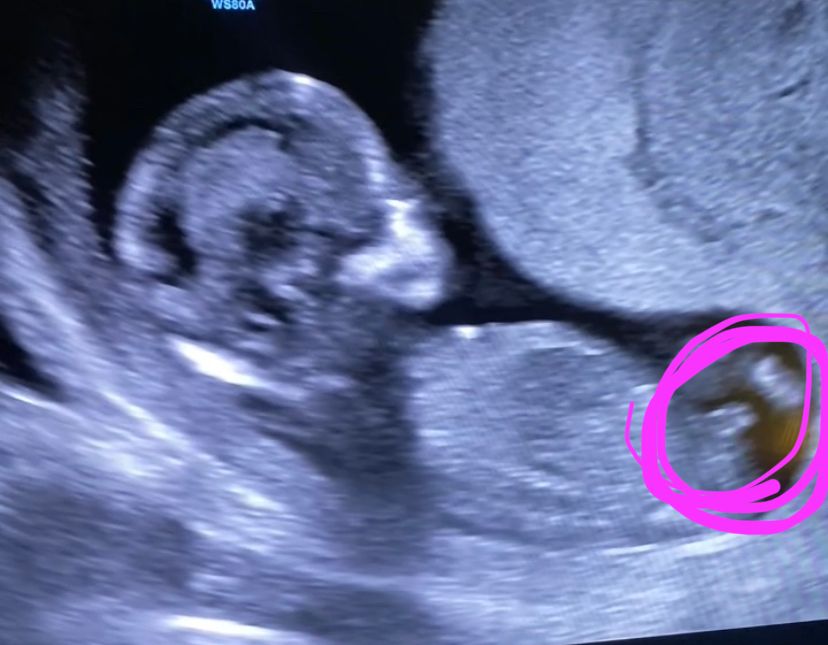

У меня так же было как у вас на первом фото обведённое розовым , в итоге девочка 😀 мне кажется у вас Девченка

Li, вот я тоже когда ЭТО увидела на узи была уверенна что мальчик наверное 😀😅

Судя по углу наклона полового бугорка - мальчик) у девочек он более горизонтально расположен